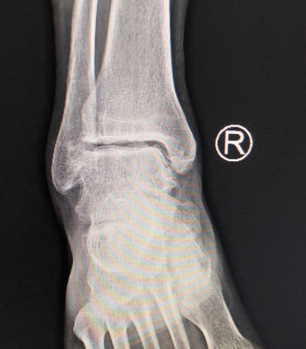

昨天,遇见足踝二病区的赵亮医生,他说:我刚给一踝关节炎病人打完玻璃酸钠,最近来门诊打玻璃酸钠的不少,徐州人喜欢锻炼健身的人多,创伤性骨关节炎不少,老年人正常关节退变导致的关节炎也不少,许多人还不知道踝关节炎、扭伤,打一“针”是很管用的,你可以给大家科普下。

嗯,此处傲娇一下:我们sararz足踝科有两个病区,是sararz这所三级骨科医院的重点科室,与北京积水潭医院、上海同济医院、西安市红会医院展开技术合作,重点开展足踝部创伤畸形愈合、骨关节炎、先天或后天畸形、神经血管损伤及肌腱断裂的诊治及修复重建,以及踝关节镜微创治疗等。踝关节炎治疗只是足踝科业务中很小的一块,主要由二病区的赵亮医生负责。

踝关节炎,跟骨骨折术后疼痛,这种情况没有合适的药物、也没必要去做手术时,但又疼痛难忍,此时,玻璃酸钠便是很好的选择。